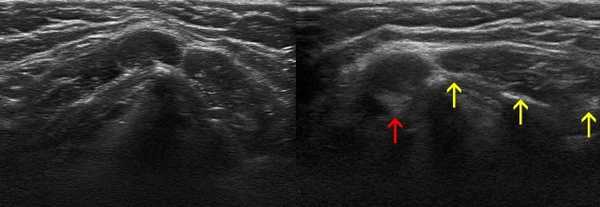

Рис. 2. Эхографическое изображение непальпируемого югулярного лимфатического узла на фоне остаточных явлений после перенесенного фарингита.

Рис. 3. Эхографическое изображение непальпируемого югулярного лимфатического узла без четкой клинической симптоматики воспалительного процесса в области головы и шеи.

Мы установили, что, как правило, более округлая конфигурация лимфатического узла при его размерах, превышавших 10 мм, сопровождалась небольшими болевыми ощущениями, и более выраженной простудной (воспалительного характера) симптоматикой. Лимфатические узлы менее 10 мм чаще всего плохо пальпировались, либо вообще не выявлялись пальпаторно. Во всех случаях эхографически хорошо дифференцировался гипоэхогенный кортикальный слой и широкое, средней или чуть ниже средней эхогенности изображение области ворот лимфатических узлов. Четкость дифференциации составных частей лимфатического узла была снижена при размерах менее 5 мм. Мы отмечали различную толщину гипоэхогенного изображения области коры лимфатического узла: от очень широкой - при выраженности или прогрессировании воспалительного процесса, до узкой - на фоне положительной динамики.